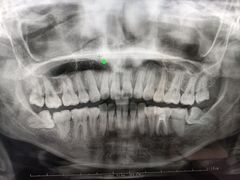

• 牙博士口腔品牌连锁(杨浦店)

• -牙博士口腔品牌连锁(杨浦店)

胸背腿 | 23-04-12